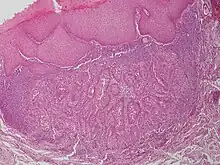

Warty dyskeratoma

Warty dyskeratoma, also known as an Isolated dyskeratosis follicularis,[1]:777 is a benign[2] epidermal proliferation with distinctive histologic findings that may mimic invasive squamous cell carcinoma[3] and commonly manifests as an umbilicated (Having a central mark or depression resembling a navel) lesion with a keratotic plug,[4] WD have some histopathologic similarities to viral warts but it's not caused by HPV and the majority of these lesions display overall histopathologic features consistent with a follicular adnexal neoplasm.[5] Usually limited to the head, neck,[6] scalp[7] or face and vulva.[6] Lesions are generally solitary and sporadic and may be associated with a follicular unit. Oral involvement,[4] particularly the hard palate, and genital involvement have been reported. it can also be thought of as one of the manifestations of focal acantholytic dyskeratosis, an epidermal reaction pattern that can be seen in several disorders, including Darier's disease and Grover's disease.[8]:639 But the main Difference between Darier disease and Warty dyskeratoma, is that Darier disease inherited dermatosis (autosomal dominant) consisting of multiple keratotic papules on the face, trunk, and extremities, while WD occurs as an isolated, noninherited, single keratotic nodule mainly confined to the head and neck as mentioned earlier.[6]